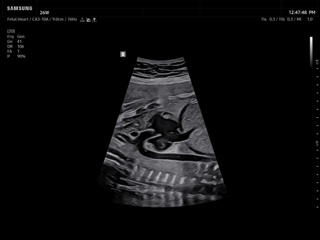

Atlas of ultrasound images - obsterics

In the section "Оbsterics" of atlas the results of ultrasonic examinations of pregnant women with different durations of gestation are represented. Here you can see images of internally organs, cerebrum, cordis and the sex of the fetus, the sonograms of multiple pregnancy, the blood flow in placenta and umbilical cord, defects of fetal`s development, etc.